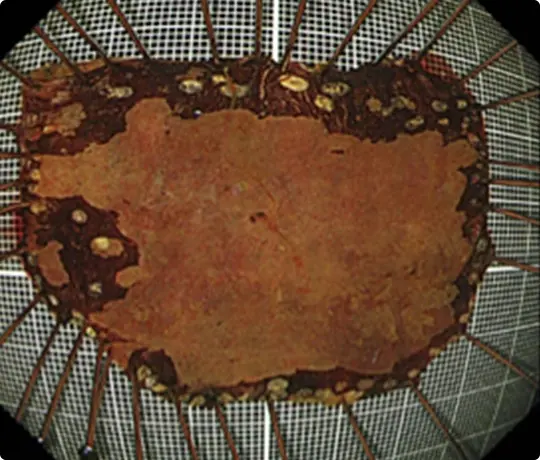

切除した検体です。病理検査で早期大腸がんと診断されました。がんは完全に切除されており、治癒と判定されました。

切除した検体をピンで伸ばして、ホルマリンで固定後、病理診断を行います。中央に見える赤く隆起している部分が腫瘍です(青い色素をかけています)。

切除した検体です。

切除した検体を展開し、ピンで伸ばしてヨード染色をしています。黄色いところが食道がんの部分です。ホルマリンで固定後、病理診断を行います。病理診断で腫瘍は完全に切除されており、治癒と判定されました。

切除した検体をピンで伸ばしています。ホルマリンで固定後、病理診断を行います。病理診断で腫瘍は完全に切除されており、治癒と判定されました。

切除した検体をピンで伸ばしています。ホルマリンで固定後、病理診断を行います。病理診断で腫瘍は完全に切除されており、治癒と判定されました。